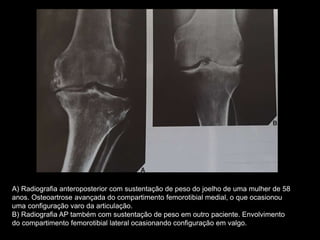

A) Radiografia anteroposterior com sustentação de peso do joelho de uma mulher de 58

anos. Osteoartrose avançada do compartimento femorotibial medial, o que ocasionou

uma configuração varo da articulação.

B) Radiografia AP também com sustentação de peso em outro paciente. Envolvimento

do compartimento femorotibial lateral ocasionando configuração em valgo.

Osteoartrose avançada nos 3 compartimentos.